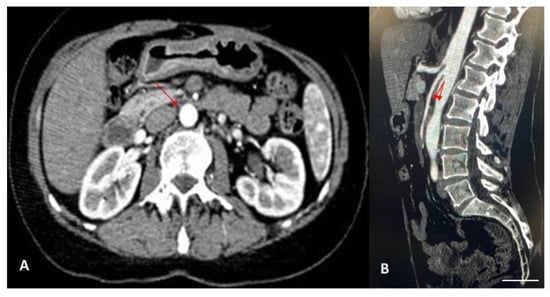

| Farina et al., 2020 [20] | 27-year-old male | Painful postprandial crises at the sub-acute onset, located at the epigastrium | Doppler US CT | Endovascular stent grafting |